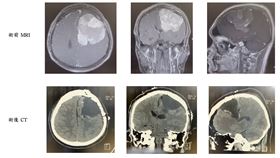

右半身無力拖延半年 醫一看:7公分腦瘤

家住雲林22歲的李姓患者於今年二月開始出現右半身無力...